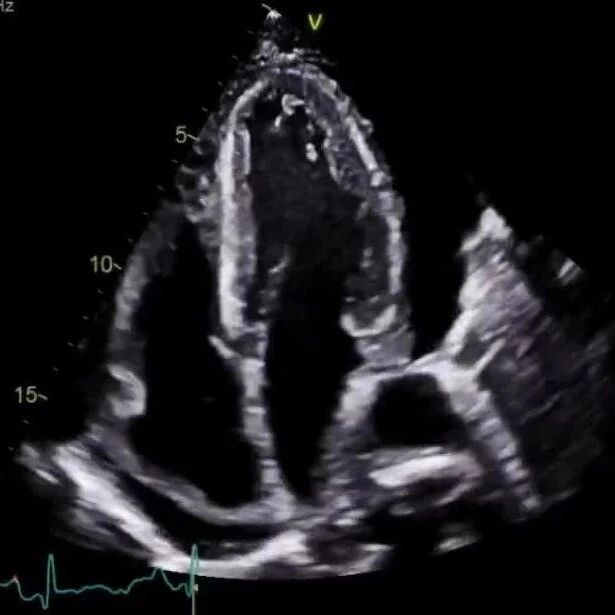

讲座 | 为什么心包积液很少位于左心房后壁?